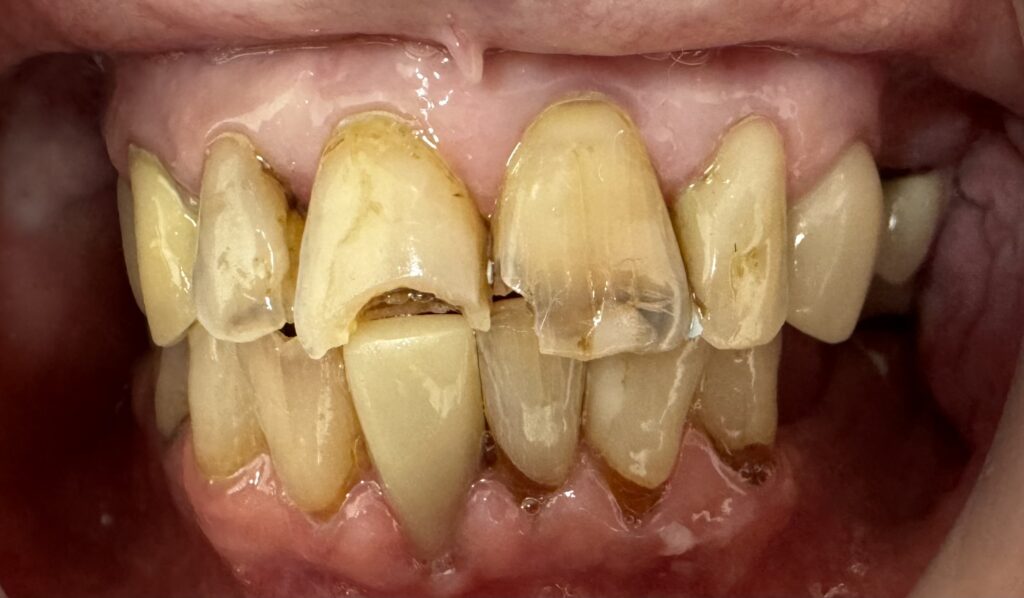

The Challenge The patient arrived at Serenity Dental Spa with a single, pronounced source of self-consciousness: a discolored and noticeable composite filling on a prominent